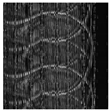

| Original Image | Marked Image | Encrypted Image (DRPE) | Decrypted Image | Correlation between Extracted Blocks and Original Blocks |

![]() | ![]() PSNR = 34.26 dB SSIM = 0.96 | ![]() PSNR = 12.84 dB SSIM = 0.0349 | ![]() PSNR = 34.37 dB SSIM = 0.96 | ![]() |